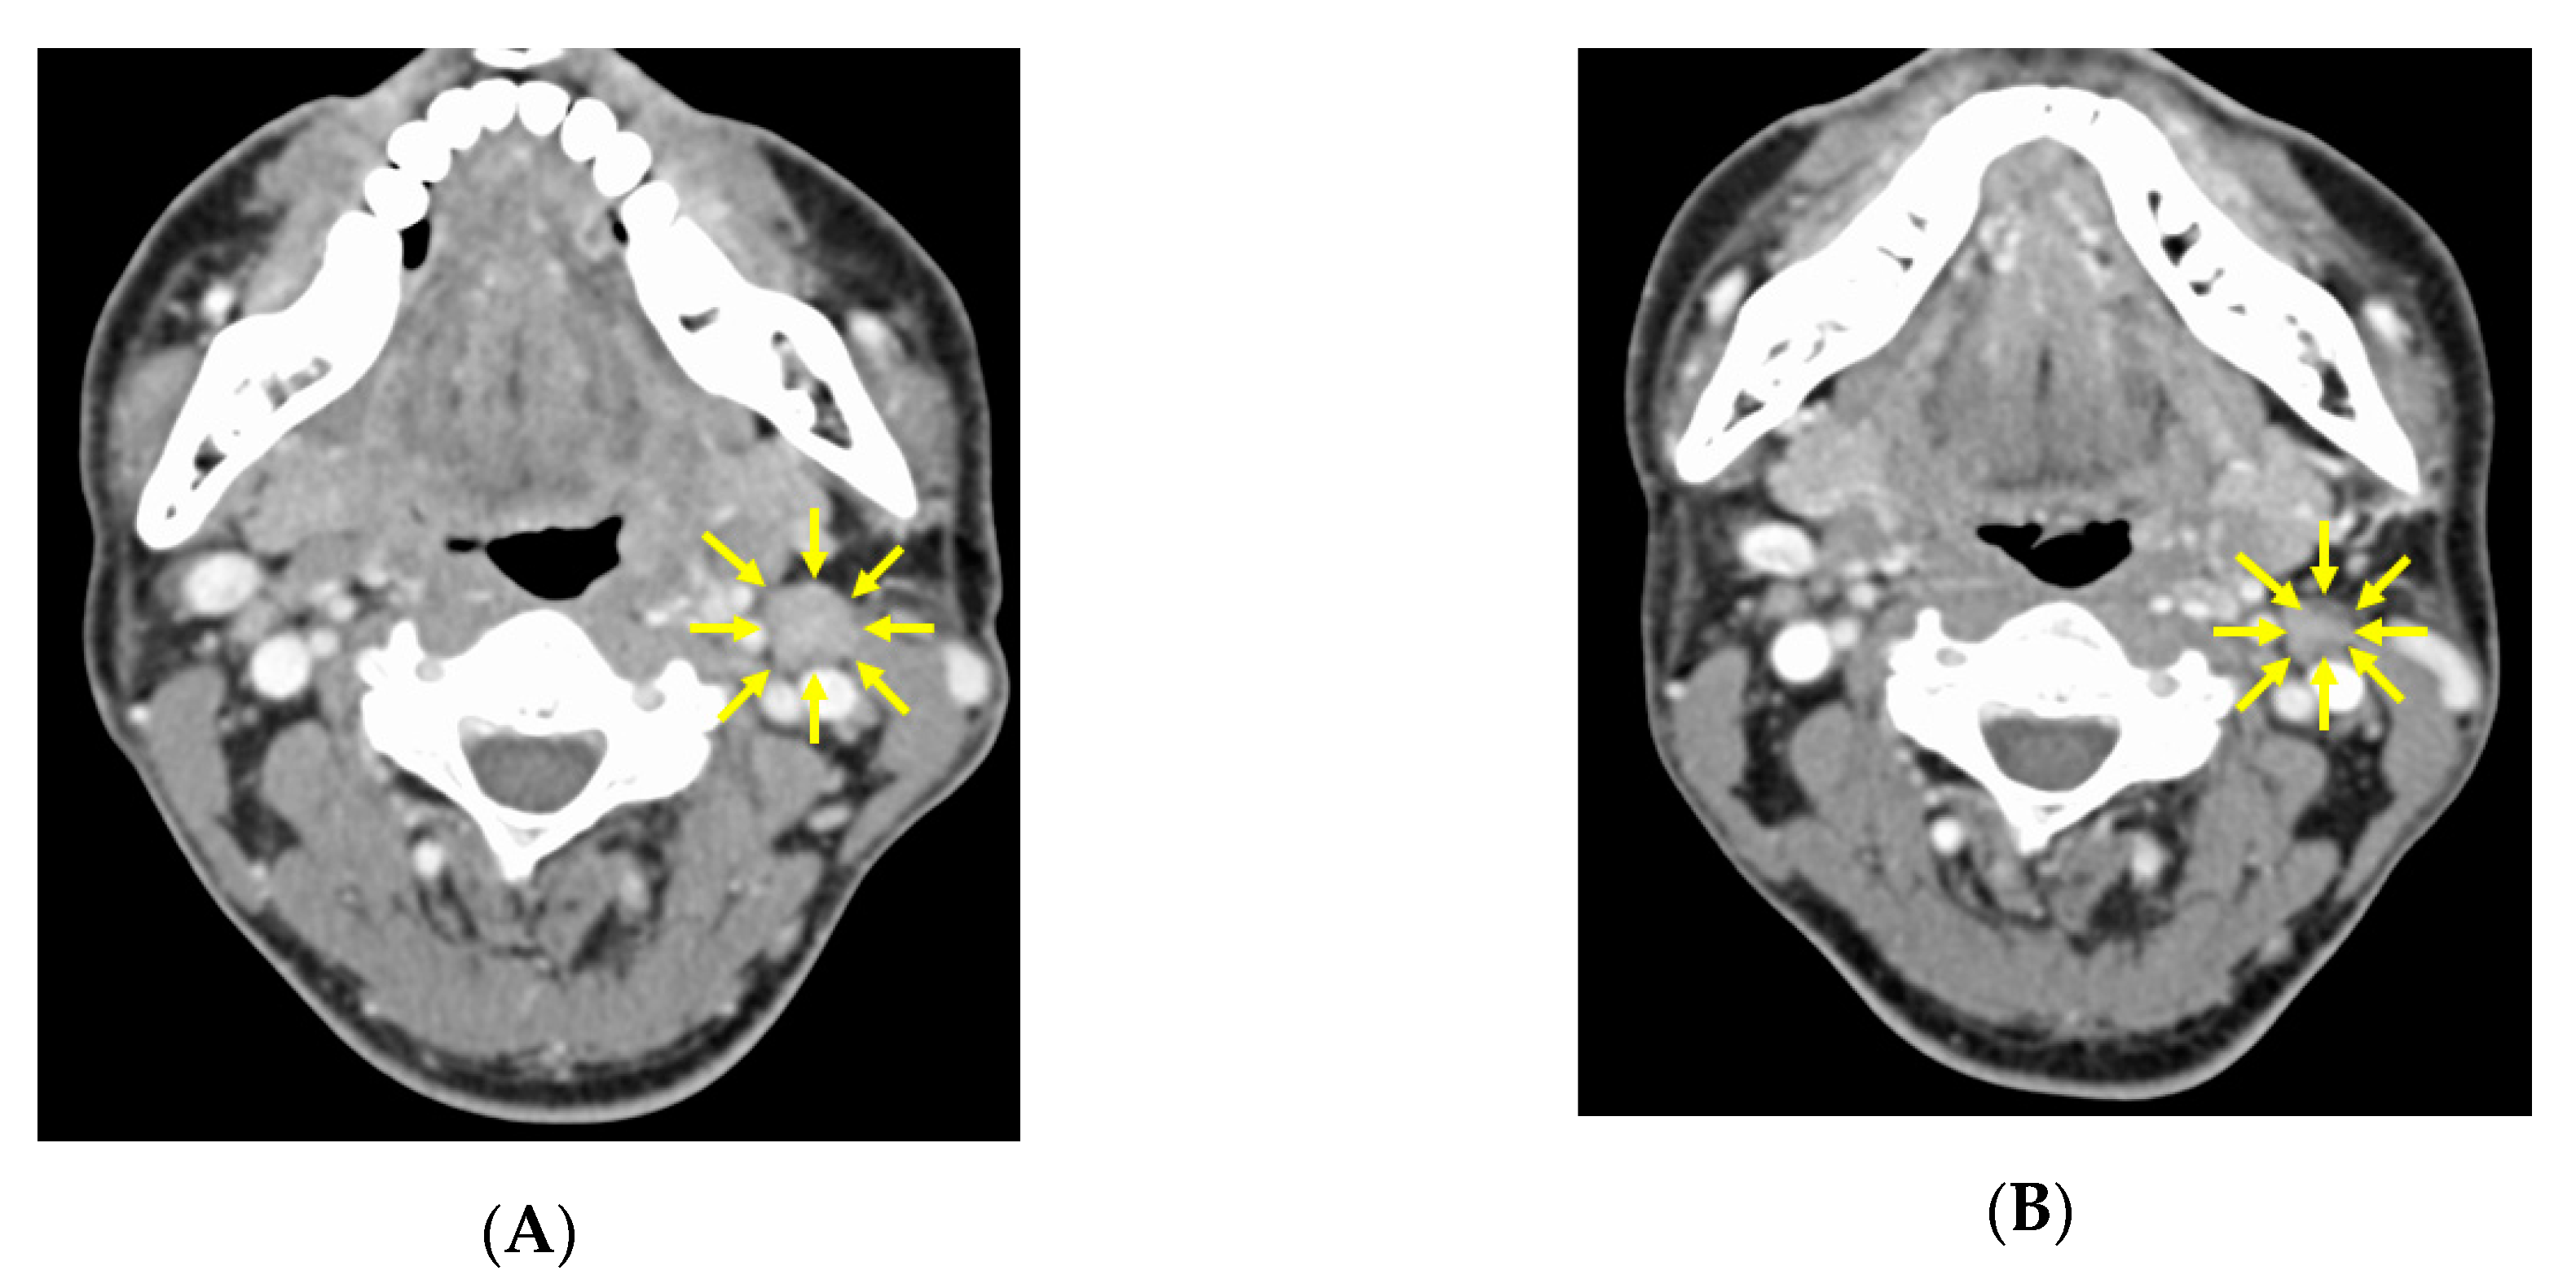

3.2. CT image Findings before and after Neoadjuvant Chemotherapy